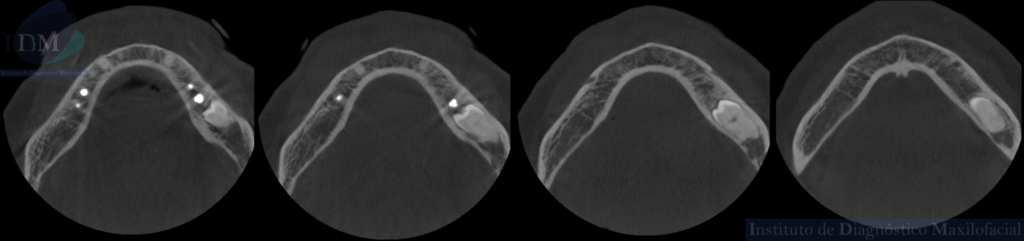

CORTES AXIALES

A la evaluación de la radiografía panorámica se evidencia reabsorción ósea alveolar bimaxilar, edéntulo parcial bimaxilar y presencia de múltiples implantes con prótesis sobre implantes así como tratamientos restaurativos. Siendo lo más destacado una molar retenida en cuerpo mandibular izquierdo, la cual esta mesioangulada.

Siendo así que en la tomografía volumétrica de haz cónico se evidencia una hipercementosis radicular, con los segmentos radiculares contactando con el conducto dentario inferior. Finalmente se evidencia un borramiento del espacio del ligamento periodontal compatible con anquilosis dentaria.